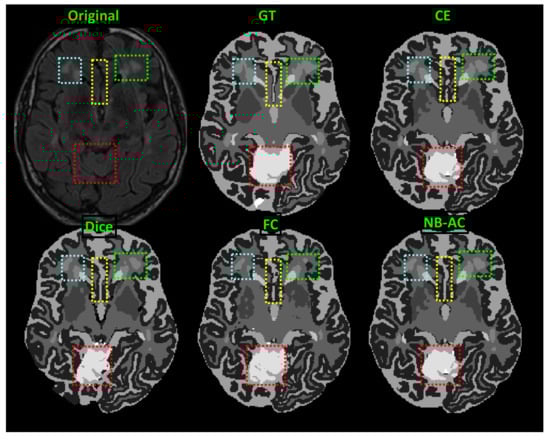

In Figure 8, the weak boundary vessel is highlighted in colored boxes. In such colored boxes, we can see the vessel is shown with poor contrast in the original image and the ground truth of the vessel is very thin. Far apart from other loss functions which are unable to capture such information, the proposed NB-AC has high capability to work in the case of weak object boundary segmentation. Not only for weak object boundary but also imbalanced-class data, Figure 9 and Figure 10 contain the performance of the middle slide of each image/volume that are from the MRBrainS 2018, BRATS 2018 datasets. In each figure, the colored boxes highlight areas corresponding to small class data and weak boundary object (especially the object boundary). Compared against other loss functions, our NB-AC loss obtains the closest result to the ground truth in both cases of weak boundary object and small object.

Clearly, comparing with the common segmentation losses, the proposed NB-AC loss improves the segmenting performance using the same network backbone. Take CE loss function as an example, the proposed NB-AC loss improved the segmentation accuracy regardless of the backbone networks (2D-FCN, 2D-Unet or 3D-Unet). Figure 8, Figure 9, Figure 10 and Figure 11 visualize the comparison between our loss and other loss functions. In these figures, some regions are highlighted to easily see the difference in segmentation results between loss functions.

Figure 9. Comparison between our results against other loss functions on the Unet framework. The image is from the MRBrainS 2018 dataset.

Figure 10. Comparison between our results against other loss functions on Unet framework. The image is from the BRATS 2018 dataset.